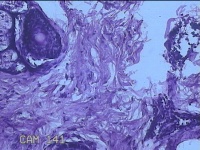

性别

男

年龄

23岁

临床诊断

右耳部肿物

一般病史

右耳前无痛性肿物20余年。

标本名称

大体所见

灰白暗红色肿物0.7x1.5x0.2cm一个,表面糜烂。

组织没固定好